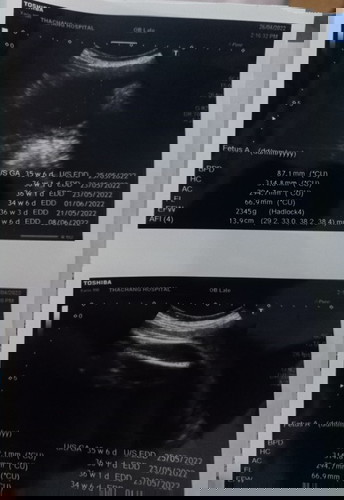

สวัสดีค่ะ พี่ๆพอดูออกมั้ยค่ะว่าน้องเป็นผู้ชายหรือผู้หญิง 😁ตอนนี้37w3D ซาวน้องแล้วขาน้องบัง

พอดีฝากโรงพยาบาลกะว่าไว้ลุ้นตอนคลอด แต่อีกใจก็รู้ ว่าน้องเป็นช.ญ☺️

มองไม่เห็นเลยค่ะแม่